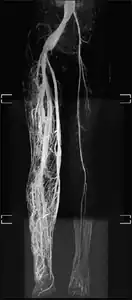

MRI: This is a high-resolution scan that is used to identify the extent of the hypertrophy or overgrowth of the tissues. This can also be used to identify other complications that may arise a result of hypertrophy.[23]

CT/CAT scan: this scan is especially useful for examining the areas affected by PWS and is helpful for evaluating the bones in the overgrown limb.[23]

MRI-dilated turtuous blood vessels